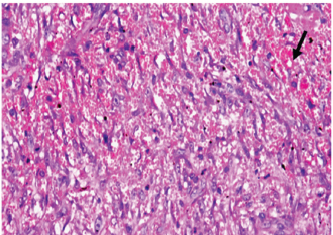

At 7 days post wounding; the inflammatory reaction was moderate and characterized by polymorphonuclear cells and macrophages infiltration with the presence of small scab covering the wound surface. Early evidence of epithelization was detected and represented by the proliferation of epidermal epithelium under the scab. There was marked thickening and hyperplastic proliferation of epidermal epithelium at the free wound edge (Fig. 6). The dermal tissue underlying the wound area showed few polymorphonuclear cells infiltration and more abundant mononuclear cells. Fibroplasia and angiogenesis were detected in the dermis and more extensive in deeper areas of the dermis which characterized by fibroblast and angioblast proliferation forming immature young granulation tissue (Fig. 7). At 14 days post wounding, the wound area was covered by a complete layer of epidermal epithelium indicating a good epithelization rate of the wound. Proliferation of cutaneous appendages was detected. The newly formed epithelium was thick and showed partial keratinization and epithelial differentiated stratum containing polyhedral keratinocyte with the appearance of keratohyalin granules in their cytoplasm (Fig. 8). The dermal tissue showed deposition of parallel well organized and interconnected collagen bundles that arranged parallel to epidermis associated with enhanced angiogenesis represented by well-developed blood capillaries (Fig. 9). At 21 days post wounding, remodeling of the formed epithelium with relatively small scar formation and mild restoration of skin appendages. Keratinized and differentiated stratum comprising the covering epithelium and the newly formed skin appendages from the basal epidermal epithelium were detected (Fig. 10). The dermal tissue revealed well-formed organized tissue consisted of parallel compact and interconnected bundles of collagen with scant angiogenesis (Fig. 11). At 28 days post wounding, well-formed scar tissue covering highly cellular organized tissue was detected (Fig. 12). The dermal tissue revealed well-arranged compact collagen bundles containing scarce blood vessels (Fig. 13).

Fig. 12. Skin of a goat from electroacupuncture group at 28 days post wounding showing well-formed scar tissue (arrow head) covering highly cellular organized tissue (HE ×100).

Fig. 13. Skin of a goat from electroacupuncture group at 28 days post wounding showing well arranged compact collagen bundles (arrow head) containing scarce blood vessels (HE ×200).

The healing of wounds in electroacupuncture is improved. At 7 days, the electroacupuncture group was characterized by early epithelization and immature granulation tissue. At 14 days, covered by thick epithelization and keratinization. The dermal tissue showed the deposition of collagen and enhanced angiogenesis. At 21 days, mild restoration of skin, and the dermal tissue was a well-organized tissue, at 28 days, showed well-formed scar tissue covering highly cellular organized dermal tissue, as previously mentioned by (Wang et al., 2009) who stated that acupuncture enhances wound healing accelerators such as fibroblast growth factors and platelet-derived growth factors in experimental models.